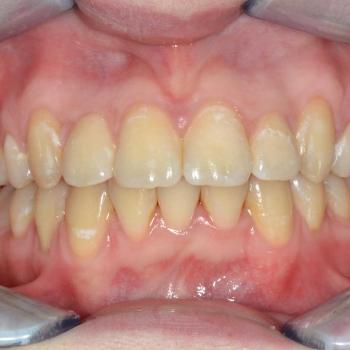

A kezelés befejeztével minden felmerülő problémát és eltérést sikerült megoldanunk, így egy funkcionálisan és esztétikailag is szép eredményt kaptunk.

A kezelés időtartama: 2 év